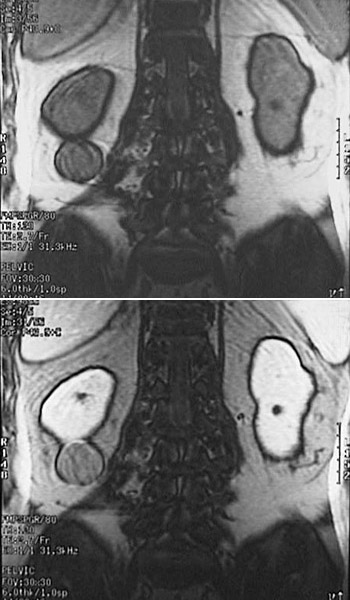

![]() | These abdominal MRI scan coronal views reveal an angiomyolipoma eccentrically positioned to the lower pole of the right kidney. These well-circumscribed tumors are histologically benign but may be multiple. They may occur in association with the rare inherited condition known as tuberous sclerosis. An incidental small simple renal cyst is also present in each of these kidneys. |